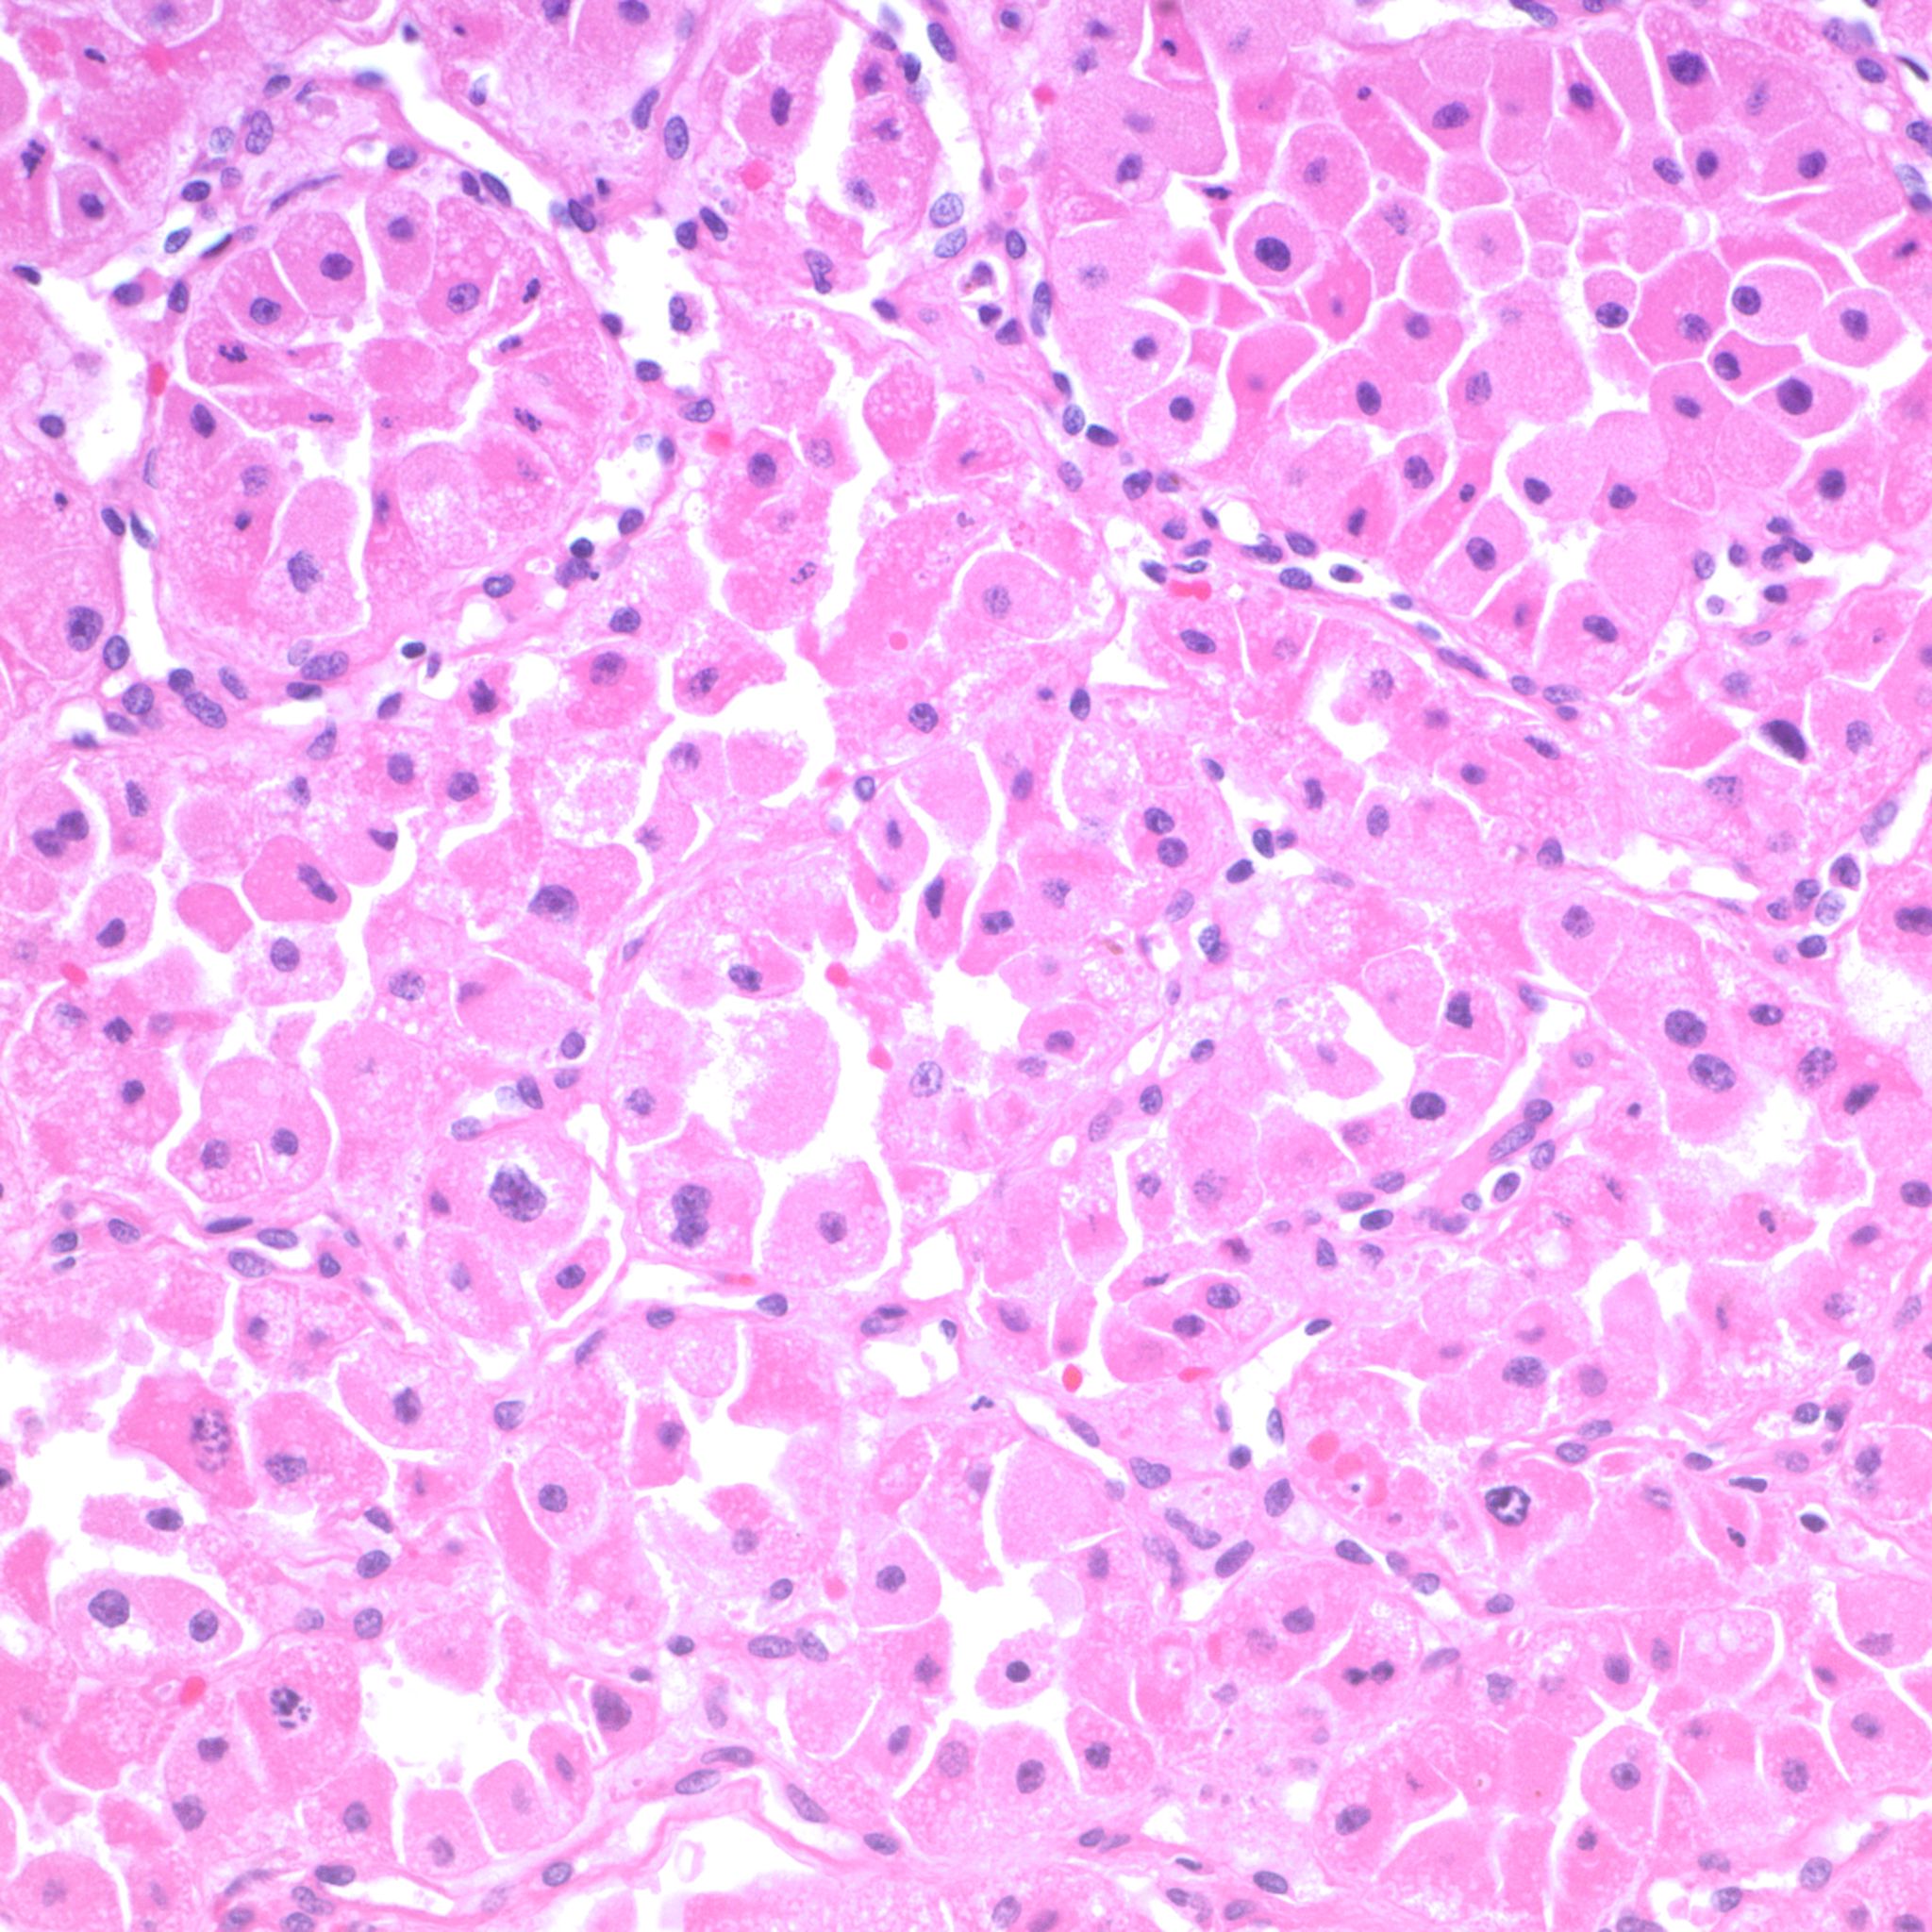

Renal tumor grading

Case ID: 1210